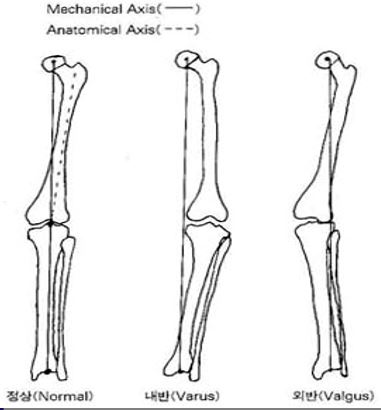

Femur head, Knee, Ankle을 연결하는 선과 ASIS에서 Tibia Tubercle을 연결하는 선이 이루는 각을 조사하여 Valgus와 Varus의 정도를 파악하는 것입니다. Hip joint부터 Knee, Ankle joint까지 모두 포함되어야 올바른 검사입니다. 그리고 모든 Joint가 true AP가 되어야 합니다. 몸이 좌우로 기울어짐이 없어야 합니다.

LONG BONE 검사의 목적은 Mechanical Axis와 Anatomical Axis의 역학적 관계를 조사하고, Valgus와 Varus의 정도를 파악하여 수술계획의 바탕을 제공함에 있습니다.

슬관절 변형의 종류는 내반슬, 외반슬, 전반슬 등 총 세 가지입니다.

1. 내반슬

- 슬관절이 외측으로 활 모양으로 휘어진 상태

2. 외반슬

- 슬관절이 과도하게 내측으로 휘어져 있는 변형